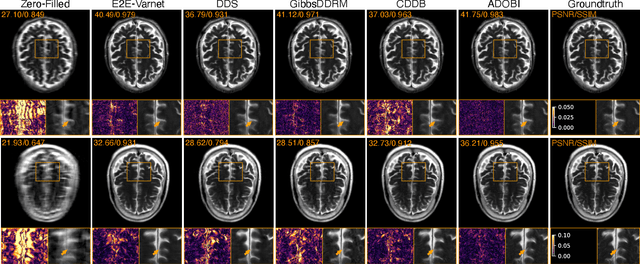

Abstract:Diffusion bridges (DB) have emerged as a promising alternative to diffusion models for imaging inverse problems, achieving faster sampling by directly bridging low- and high-quality image distributions. While incorporating measurement consistency has been shown to improve performance, existing DB methods fail to maintain this consistency in blind inverse problems, where the forward model is unknown. To address this limitation, we introduce ADOBI (Adaptive Diffusion Bridge for Inverse Problems), a novel framework that adaptively calibrates the unknown forward model to enforce measurement consistency throughout sampling iterations. Our adaptation strategy allows ADOBI to achieve high-quality parallel magnetic resonance imaging (PMRI) reconstruction in only 5-10 steps. Our numerical results show that ADOBI consistently delivers state-of-the-art performance, and further advances the Pareto frontier for the perception-distortion trade-off.